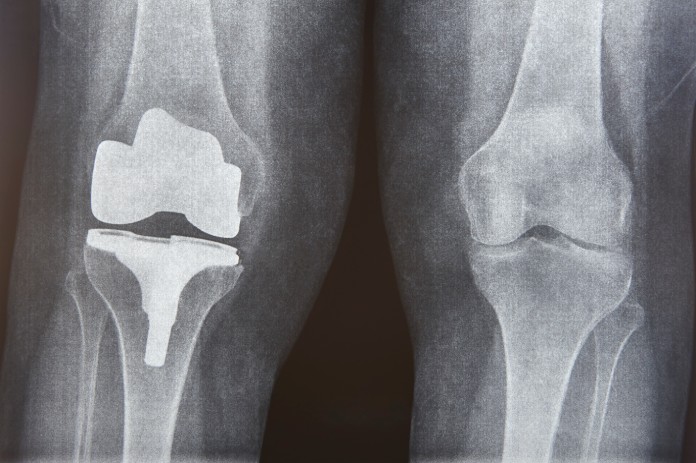

Najbolj razširjena in vidna trajna posledica športa je osteoartritis (OA). Statistike so neusmiljene: po podatkih raziskave, objavljene v American Journal of Sports Medicine, imajo nekdanji vrhunski športniki 2 do 3-krat večje tveganje za razvoj degenerativnih sprememb na sklepih v primerjavi s splošno populacijo. Najhuje so prizadeti kolena, kolki in gležnji, pri čemer študije na nekdanjih olimpijcih potrjujejo, da so prav ti nosilni sklepi tisti, kjer se biokemijski dolg kariere najprej plača. Študije, objavljene v reviji Journal of Athletic Training, razkrivajo srhljivo dejstvo o poškodbah vezi. Približno 50 % športnikov, ki utrpijo raztrganino sprednje križne vezi, razvije osteoartritis v 10 do 15 letih po poškodbi – ne glede na to, ali so bili operirani ali ne. Težava je v tem, da operacija povrne stabilnost, ne more pa povrniti prvotne biokemije sklepne tekočine. Na mestu poškodbe ostanejo kronični vnetni markerji, ki kot rja razjedajo hrustanec, dokler edina rešitev ne postane umetni sklep. Športniki po podatkih British Journal of Sports Medicine v povprečju potrebujejo umetni sklep bistveno prej kot njihovi manj aktivni vrstniki, kar potrjuje dejstvo o pospešeni mehanski obrabi.

Hitrejša obraba sklepov pri športnikih vodi v hitrejšo menjavo sklepa z umetnim. Foto: Envato